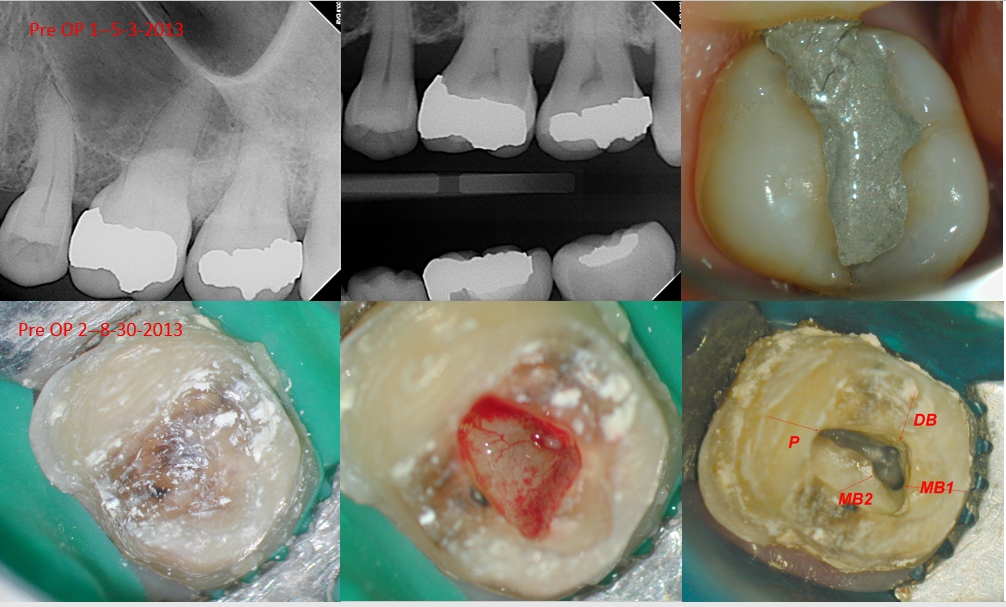

This patient was referred to me by the Prosthodontist next door for evaluation on teeth #14 and 15 prior to crown fabrication. My examination revealed signs consistent with reversible pulpitis. I asked the RD to prep the teeth, temporize and have me re-evaluate. If the symptoms worsened, I would perform endodontic treatment on one, or both teeth. Patient returned three months later, with excruciating pain in both of her molars. Treatment was initiated and completed two weeks later. I love the photograph of the vascular system when I opened tooth #14, looks cool!

the buccal canals were shaped to a 17/.04 VTapers, and the palatal to a 20/.06 VTaper. I saw the patient for a 6MO Recall, a one year recall, and 2,3,4.5 year recall (she missed her 4 year recall) and I should be seeing her in a few months for her 5.5 year recall (I hope the tooth is still there and is still asympomatic).